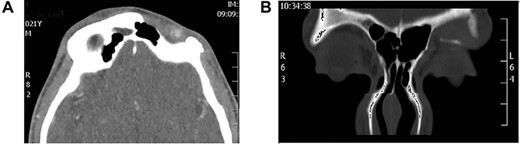

Case 5: frontal bone osteomyelitis with frontocutaneous fistula

Young man complaining of chronic left frontal pain with discharging fistula above his left eyebrow. CT scan showed an inflamed frontal bone secondary to his frontal sinusitis (Fig. 5A). Coronal CT sinuses (Fig. 5B) confirmed the diagnosis of frontal osteomyelitis and discharging frontocutaneous fistula. The patient underwent endoscopic sinusotomy with external debridement of infected frontal bone with closure of fistula. Patient improved with no evidence of recurrence.

(A) Axial CT scan showing left frontal bone osteomyelitis and (B) CT sinuses showing left frontal bone osteomyelitis with discharging fistula.